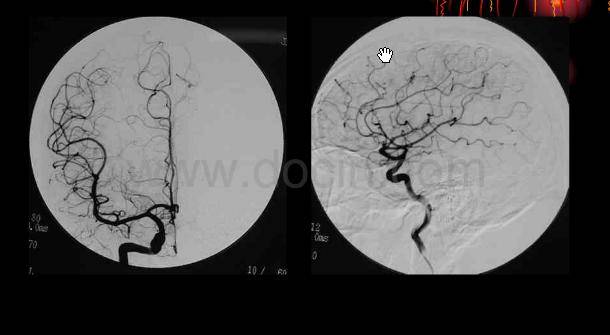

[经验交流]后交通动脉瘤一些dsa图片

dsa正位造影显示右侧颈内动脉急性闭塞.

12床都散希力甫汗 左侧颈内动脉动脉瘤 复查dsa(副本)